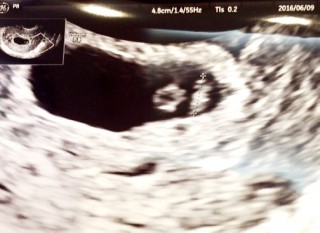

生理予定日から1週間、少し早いけど産婦人科受診しました。胎嚢と卵黄嚢は見えるね~と先生。赤ちゃんは、まだ見えないからまた2週間後ね、と。 早く赤ちゃんの心拍確認できますように!